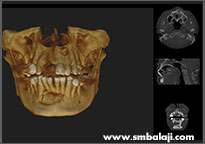

3D Cone Beam CT image (CBCT) showing extensive cyst in lower jaw middle region and upper left jaw

Digital X-ray showing cyst lesions